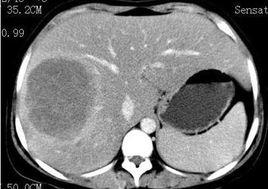

肝細胞染色較淺,漿膜明顯,因胞漿內充滿糖原而腫脹且含有中等或大的脂肪滴,其細胞核亦因富含糖原而特別增大。細胞核內糖原累積、肝脂肪變性明顯但無纖維化改變是本型突出的病理變化,有別於其他各型糖原累積病。

臨床表現輕重不一:重症在新生兒期即可出現嚴重低血糖、酸中毒、呼吸困難和肝腫大等症狀;輕症病例則常在嬰幼兒期因生長遲緩、腹部膨脹等就診。由於慢性乳酸酸中毒和長期胰島素/胰高糖素例失常,患兒身材明顯矮小,骨齡落後,骨質疏鬆。腹部因肝持續增大而膨隆顯著。肌肉鬆弛,四肢伸側皮下常有黃色瘤可見。但身體各部比例和智慧型等都正常。患兒時有低血糖發作和腹瀉發生。少數幼嬰在重症低血糖時尚可伴發驚厥.但亦有血糖降至0.56mmol/L(10mg/dl)以下而無明顯症狀者。隨著年齡的增長,低血糖發作次數可減少。由於血小板功能不良,患兒常有流鼻血等出血傾向。